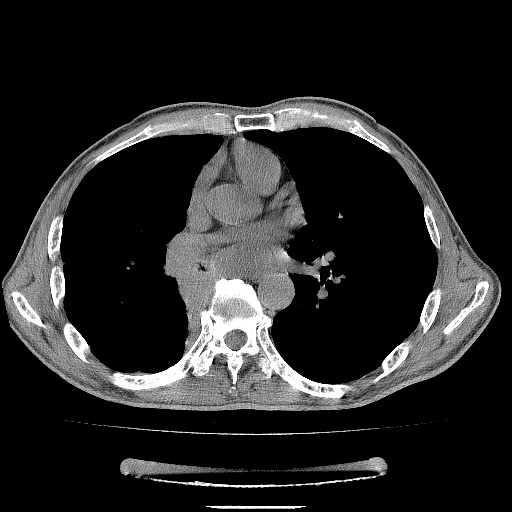

男性患者,63岁。右侧胸背部疼痛2月,加重一周。

考虑:右肺中央型肺癌并右肺下叶不张;两肺尖继发性肺结核。

还有纵隔多处肿大淋巴结及肋骨的改变、两肺多发结节灶。

考虑右中心型肺癌并右下肺不张,肺及纵隔,左肋骨转移。

右肺下叶支气管狭窄闭塞,右下肺不张,气管前间隙淋巴结肿大,两上肺散在分部粟粒灶,沿肺血管支气管束分部,血管支气管束走形较为光滑。考虑右肺中心型肺癌合并肺不张,纵隔淋巴结转移,两上肺癌性淋巴管炎

右肺下叶中心性肺癌并纵隔淋巴结转移,左侧肋骨转移。双肺上叶继发性结核表现。

1)右肺下叶中心性肺癌并纵隔淋巴结转移,两肺转移,左侧肋骨转移。2)双肺上叶继发性结核。

右肺下叶中心性肺癌并纵隔淋巴结及两肺、左侧肋骨转移。双肺上叶继发性结核表现。